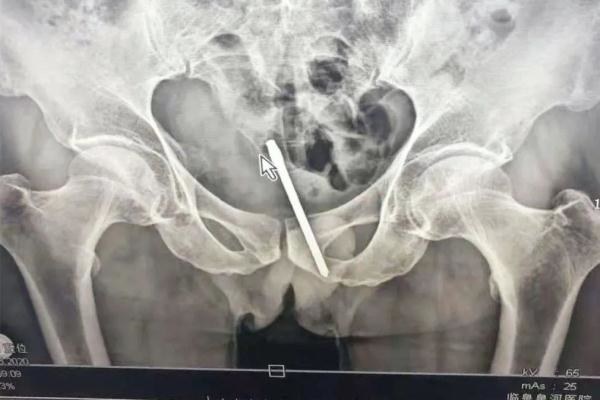

最近,根据广明网的说法,汤汤尼的祖父很多日子都不急于肛门,结果不仅是一个向量,还留下了直肠的起动器。

幸运的是,医生,医生和手术提取异物。

浙江大学,中性外科王丹阳,副运河的副轮廓,肛门管的侧管位于消化道的末端,肛门连接到直肠。直肠长度为约15至16厘米,但它被称为“直”肠道,但实际上是直的,但有三首歌。

如果从肛门插入一个长条,易于嵌入转弯,肛门括约肌就像“橡皮筋”,这使肛门闭合并关闭高达2-3厘米。有。异物夹在肛门中后,括约肌关闭,因此难以去除前景。

更糟糕的是,异物侵犯肛门和患者会紧张。目前,异物向内推动。如果您使用过使用,可以将异物推入更深层次的地方。到达雷克底部 - 这个地方很难“拯救”事情并取出东西。